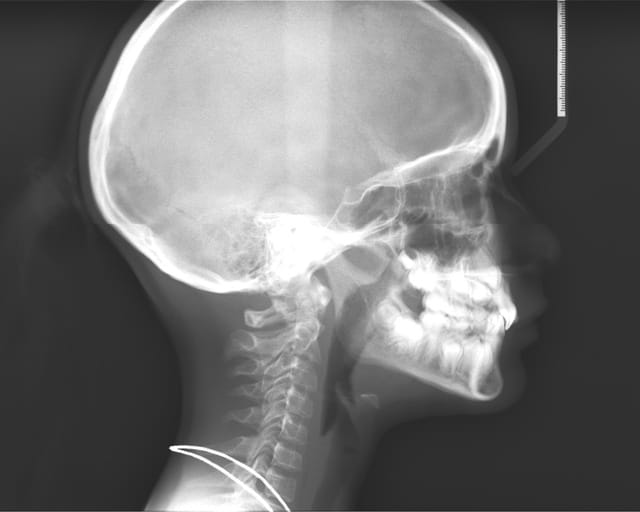

Radio t l  de profil tcayab - Eugenol

Elle présente une linguo-version et une égression des incisives maxillaires et mandibulaires. Le truc c'est que les racines de 11 et 21 semblent bien positonnées sur la télé de profil, alors que les faces vestibulaires sont très lingualées.

je pense que tu as mal regardé ta télé et que tu t'es fait avoir par la superposition des latérales et des centrales.

je crois que la forme très bombée de la couronne de centrale sur la radio, et qu'on ne voit pas sur les photos, est due à la superposition des quartes inciives. Quand au traitement, il s'agit d'un traitement classique d'un cas de classeII div 2.

Attention quand même aux racines des centralesavant de commencer, une retroalvéolaire pourrait être utile.

regarde bien la téléradio on voit la racine des centrales avec leur apex face vestibulaire de la canine définitive

Il n'y a pas de doute les racines sont normales : car si il y avait un angle si prononcé entre l'axe radiculaire et l'axe coronaire,elles paraîtraient beaucoup plus courtes sur la pano ou la télé de face.